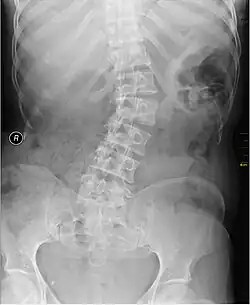

Kyphosis (left) and scoliosis (right) depicting iliocostal contact (a) | |